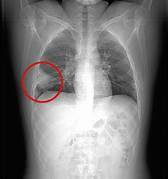

O que é sinal da silhueta? Quais são as causas? Perda da definição de uma estrutura, associada a consolidações ou massas. Pneumonia, derrame pleural e neoplasias.

Que sinal é esse? Sinal da silhueta

O que é o sinal da silhueta? Perda da definição de uma estrutura devido à consolidação ou massa.